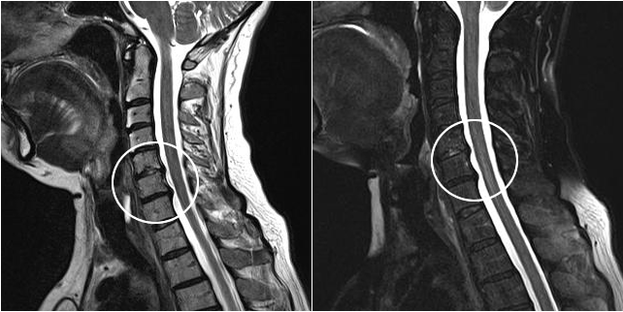

Modern diagnostic methods include MRI and CT, which make it possible to more accurately examine the destruction processes of cartilage and bone tissue.Additionally, using this technique it is convenient to diagnose hernias and other soft tissue defects close to the origin of the disease.